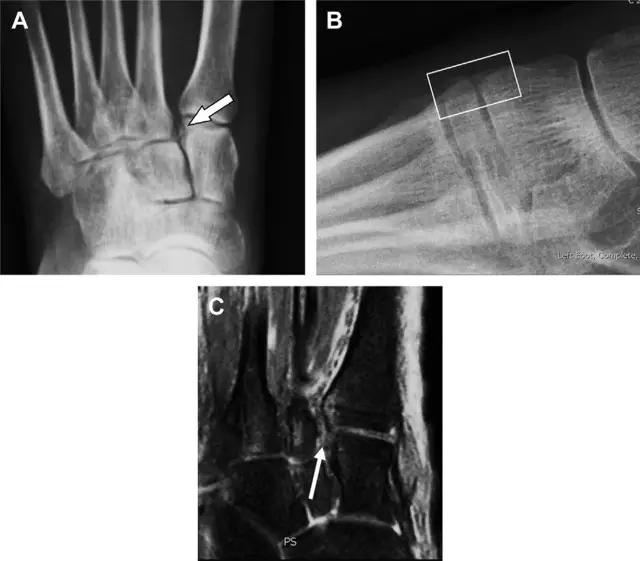

与跗跖关节韧带相关的骨折常由旋前或旋后的跖屈损伤引起。尽管跗跖关节骨折脱位仅占所有骨折的 0.2%,但是约 20% 的这些骨折在初次检查时被漏诊。初次 X 片可能示正常,但是负重位 X 线片常常提示脱位或半脱位。

典型表现:第二跖骨底和内侧楔骨之间的骨折碎片,跖骨间间隙增宽(图 8)。脱位亦可发生在舟骨-内侧楔骨关节,导致另一种变异的跗跖关节损伤(图 9A)。此外,骰骨的小块皮质撕脱在足部斜位片上可清晰显示(图 9B)。

图 8 从马上摔落的患者,跗跖关节骨折。A 正位片示内侧楔骨旁边的小骨折碎片(箭头),第二跖骨底向外半脱位;B 负重位侧位片示第二跖骨相对中间楔骨向背侧轻微移位(长方形);C STIR 序列 MRI 图像示跗跖关节韧带断裂(箭头),第一至第三跖骨、内侧楔骨及中间楔骨均骨髓水肿

图 9 变异的跗跖关节骨折。A 另一种类型的跗跖关节损伤,中间楔骨向内侧半脱位(弧形箭头),从而使第一、第二跖骨间间隙变宽,需注意,骨折在靠近内侧楔骨处(箭头);B 外侧跗跖关节损伤伴随从骰骨跖骨韧带的骰骨撕脱(箭头),需注意,第五跖骨底近端处存在软组织水肿(空箭头)